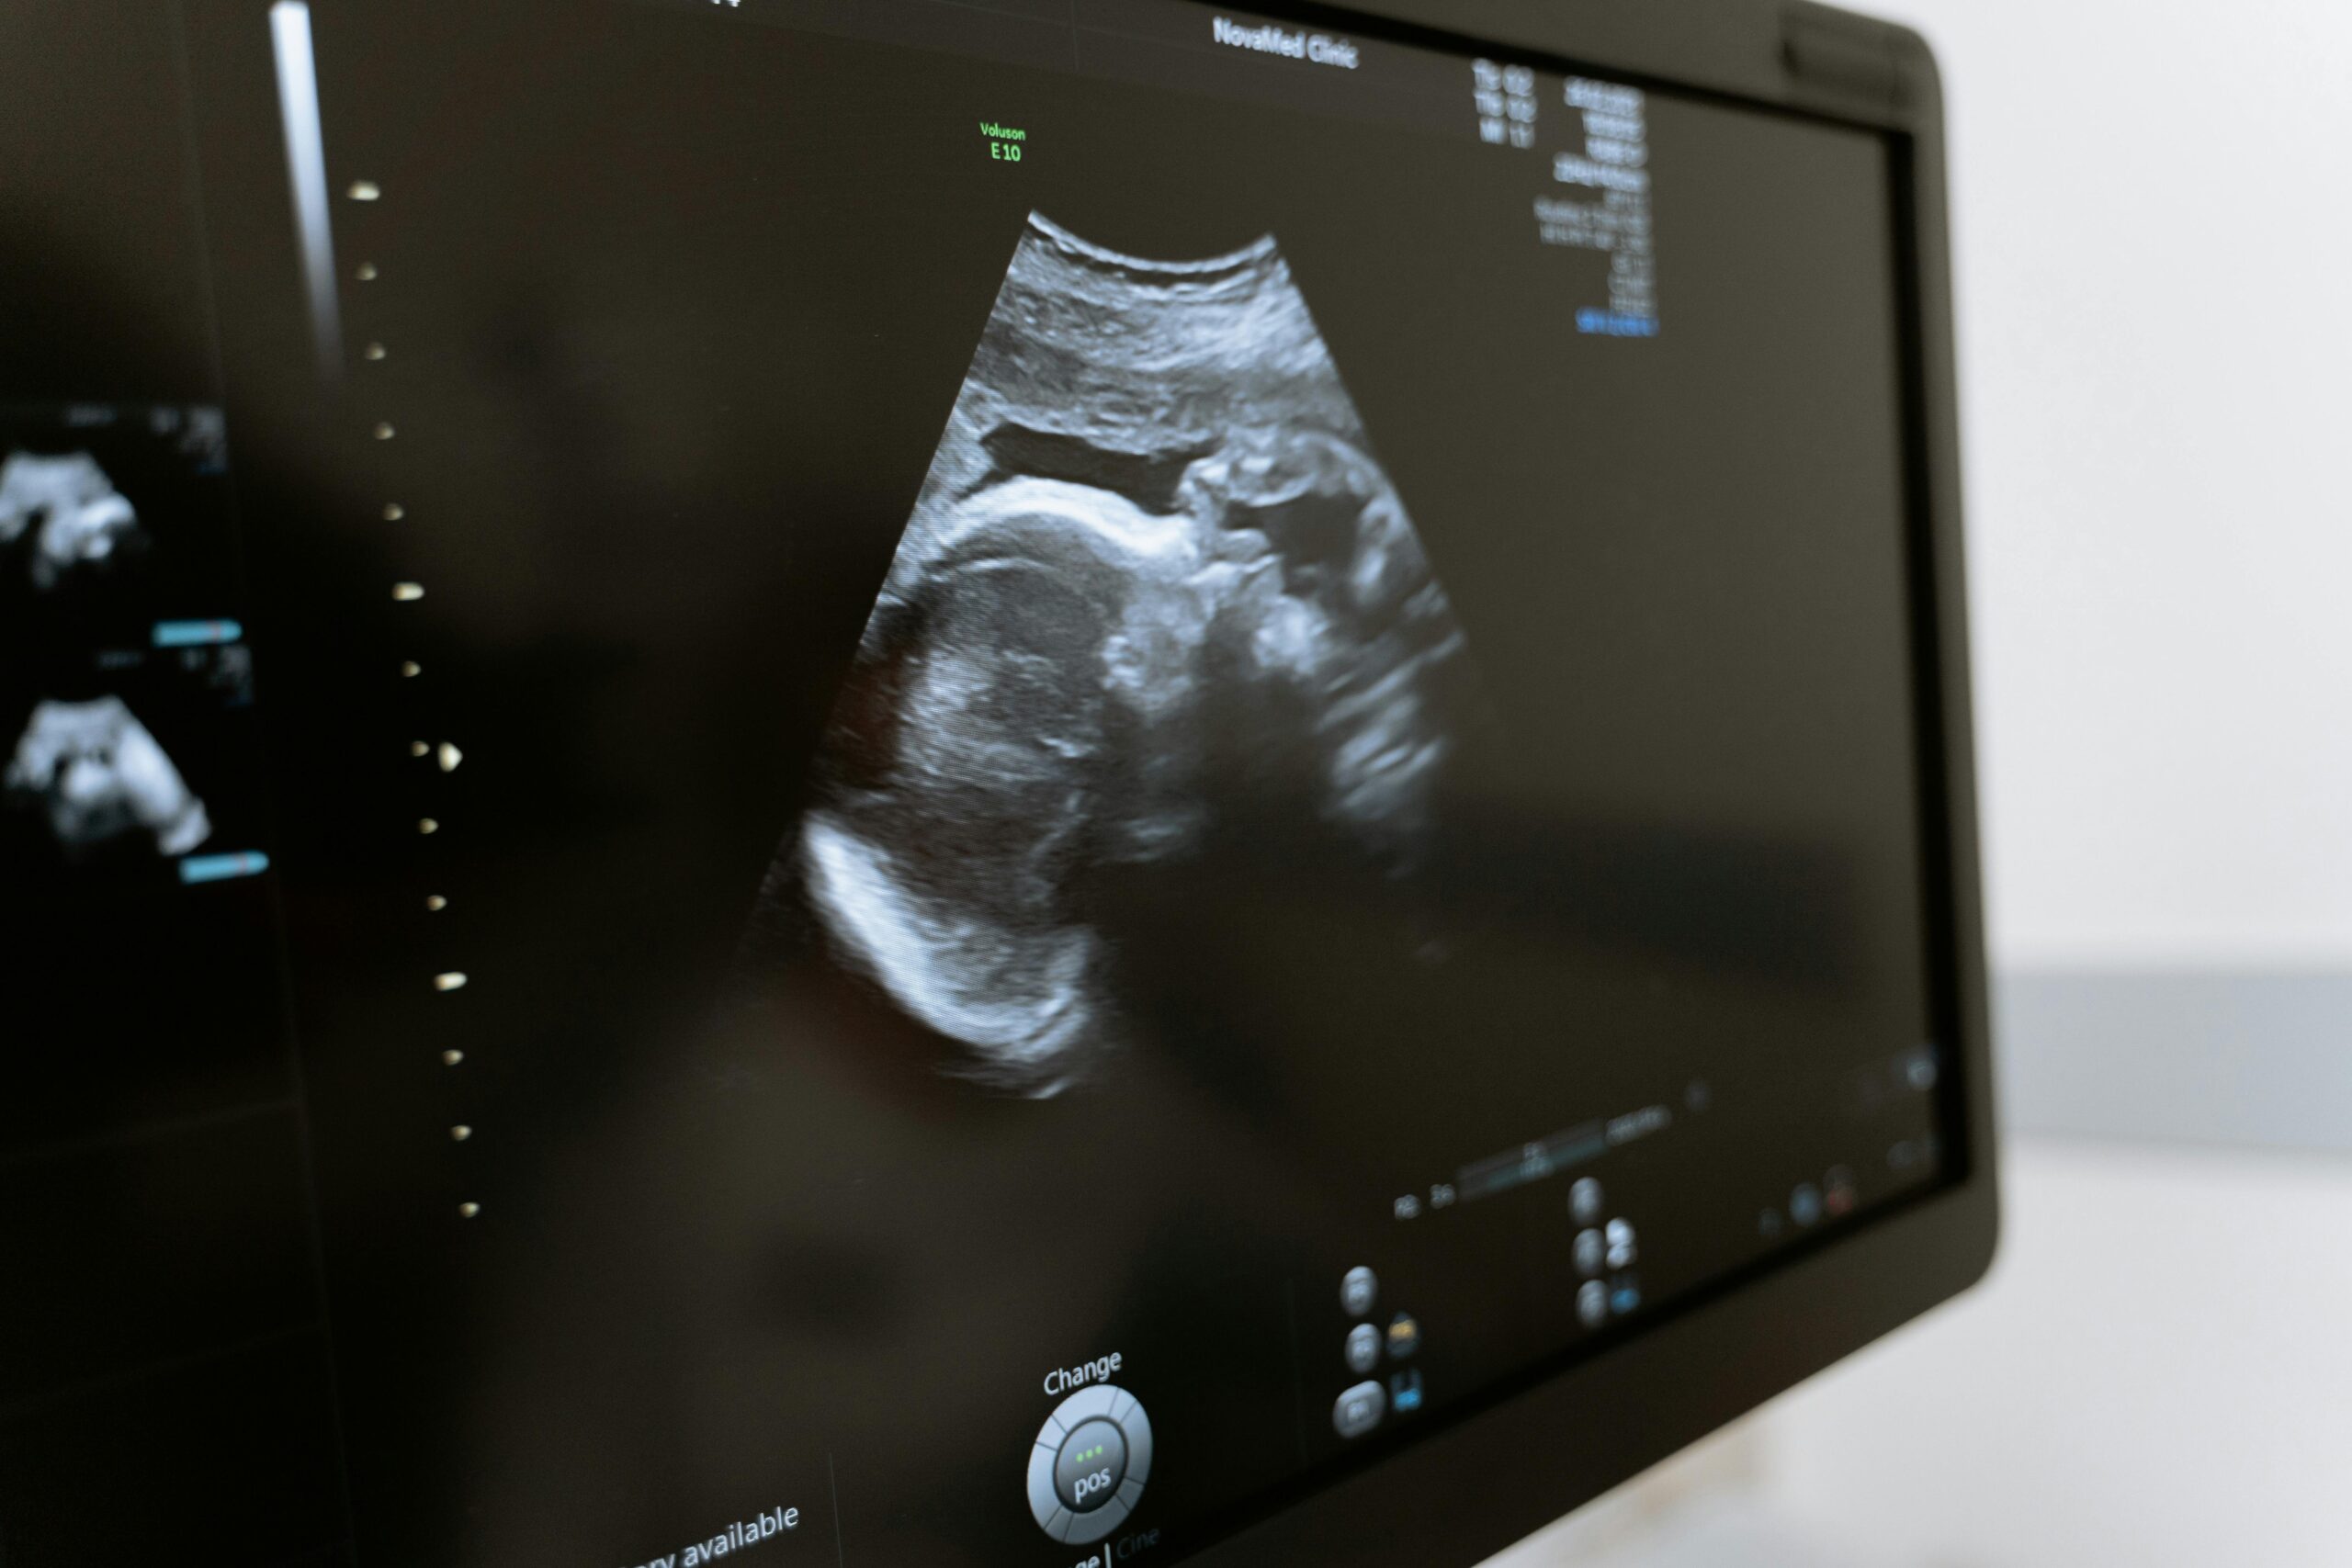

Between the 18th and 22nd week of pregnancy, a TIFFA an intricate ultrasound examination is conducted. Its purpose is to assess the fetal anatomy and detect any possible irregularities or developmental concerns.

A TIFFA scan is a detailed ultrasound performed between 18 and 22 weeks of gestation.

This non-invasive procedure offers expectant parents a comprehensive view of their baby’s well-being, providing valuable insights into various aspects of the fetal anatomy. By utilizing high-frequency sound waves, the TIFFA scan captures detailed images of the baby’s organs, limbs, and other structures within the womb. With its ability to provide precise visualizations, this advanced ultrasound technique plays a crucial role in ensuring the optimal health and development of the unborn child.